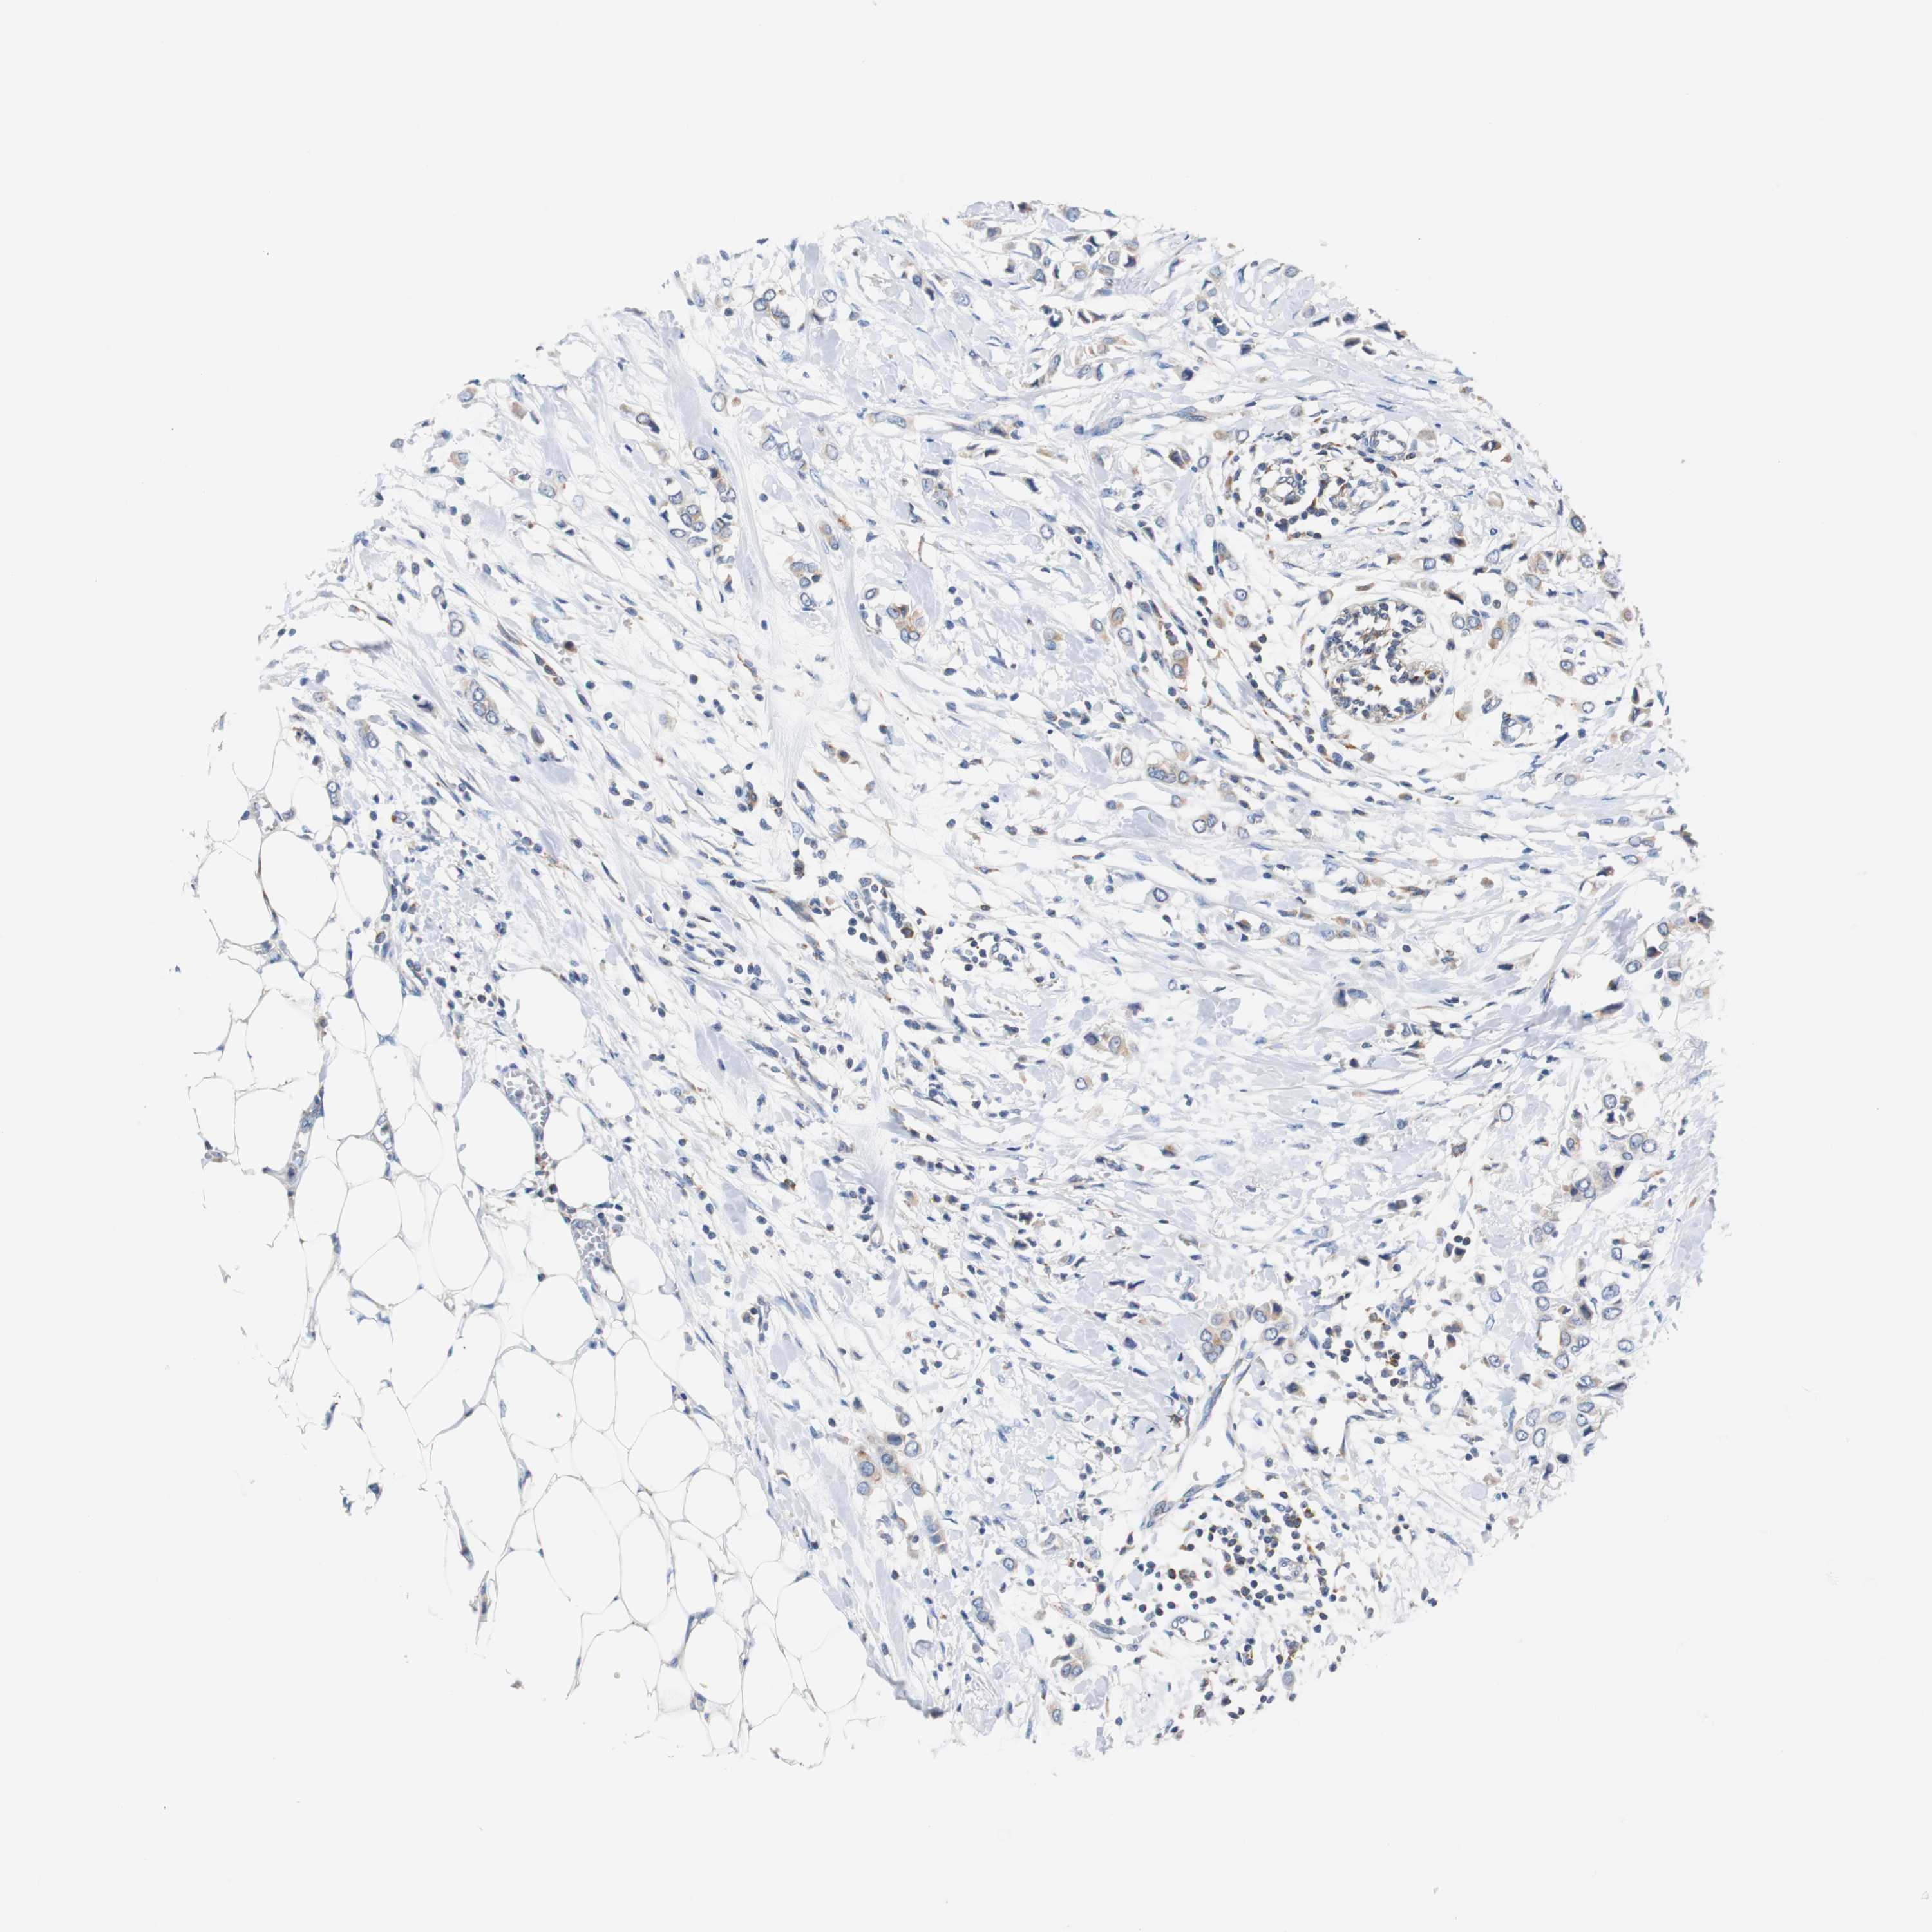

CANCER BREAST CANCER Show tissue menu

BRCA TCGA BRCA VALIDATION PROTEIN EXPRESSION

Breast cancer

Human cancer